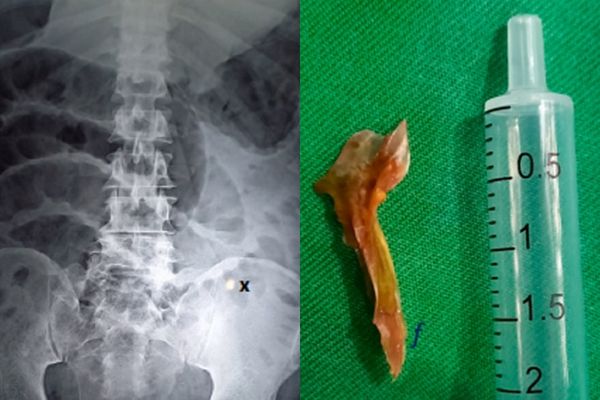

外科医生紧急替男子开刀后发现,他的肠子里居然有一根0.8英寸(约2公分)长的鱼刺,而且还穿破小肠,出现约0.2英寸的洞(约0.5公分),才会导致肠道被感染。后来医生帮男子切除了约4英寸(约10公分)的肠道,但男子依旧没有好转,最终在到院8小时候因心脏骤停而宣告不治。